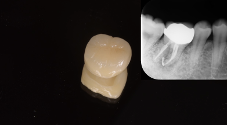

セラミッククラウンで補強し、機能・審美を回復。

根管充填後は、レジンという材料で空洞を埋め、のちに被せ物を歯に被せて一連の治療が終了します。実は、この補綴治療の質も根管治療の質と同じくらい重要であることが知られています。つまり、根管治療がうまくいっても、唾液に含まれる細菌から歯を守る第一線にいるのは被せ物(クラウン)であるためそれの質が悪い(例えば歯と被せ物の間に大きな隙間がある)と再感染を引き起こしてしまいます。

根管治療を台無しにしないように、質の良い補綴治療もセットで大事になってくることも強調したいです。

炎症を起こした神経を除去し、根管内を無菌化した上で根充およびクラウン補綴を行いました。

根管治療100,000円+ファイバーコア築造33,000円+セラミッククラウン115,500円.